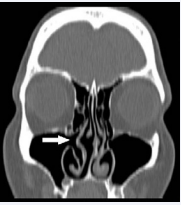

The axial CT image of the right inferior concha bullosa.

Figure 3: The axial CT image of the right inferior concha bullosa.